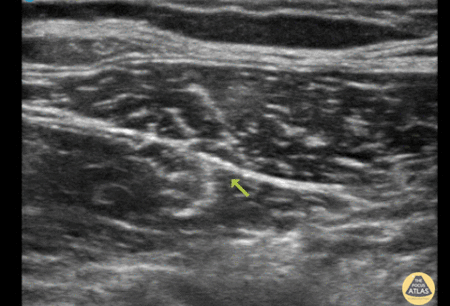

"74 male presenting with mechanical fall down twelve steps complaining primarily of severe right hip pain. X-ray demonstrating comminuted subcapital femoral neck fracture with significant angulation. In agreement with orthopedic recommendations an ultrasound-guided fascia iliaca nerve block was performed with 40cc of bupivacaine 0.25% with successful analgesia. Transverse views of the right femoral artery and vein are first identified (not shown), then translocated laterally to identify the fascia iliaca plane. Sartorius and iliacus muscles are seen above and below, respectively. An ultrasound-guided longitudinal view was utilized to introduce the needle immediately below the fascia iliaca plane and administer anesthetic." Authored by Dr. Chris Lim, Kings County Medical Center